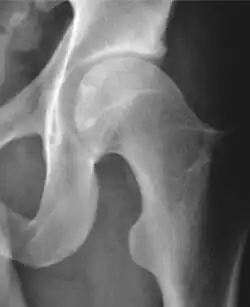

Projectional radiography ("X-ray") is often considered first line for FAI.[10] Anterior-posterior pelvis and a lateral image of the hip in question should be attained.[10] A 45-degree Dunn view is also recommended.[10][19]

| Alpha angle | ![]() |

Degree of bulging of the femoral head-neck junction: In normal conditions there is a symmetric concave contour at the junction of the femoral head and neck. Loss of this concavity or bone bulging may lead to cam type impingement. The degree of this deformity can be measured by the alpha angle. Although it can be measured in the cross-lateral view, the 45° Dunn view is considered more sensitive and the frog leg view more specific in determining pathologic values. |

|